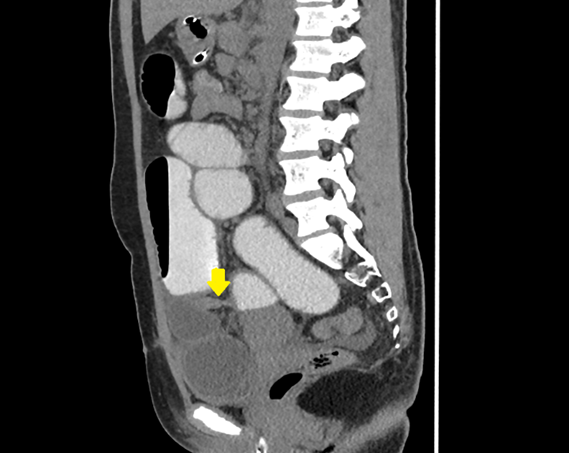

Multidetector computed tomography (MDCT) of the abdomen with oral non-ionic contrast demonstrated a tubular structure arising from the distal ileum, showing two adjacent transition points (the “double-beak” sign), a C-shaped closed-loop configuration, and convergence of mesenteric vessels toward the diverticular base. These findings were consistent with a closed-loop small bowel obstruction (SBO) secondary to Meckel’s diverticulum. [Figure 2] [Figure 3] [Figure 4]

Figure 3: sagittal CT image of the abdomen shows A fibrous band arising from a Meckel’s diverticulum (yellow arrow) is seen encircling the distal ileal loops, forming the transition point. Dilated fluid-filled loop of obstructed small bowel below this point, consistent with a closed-loop obstruction., contrast-filled proximal small bowel loops are observed above the site of obstruction.